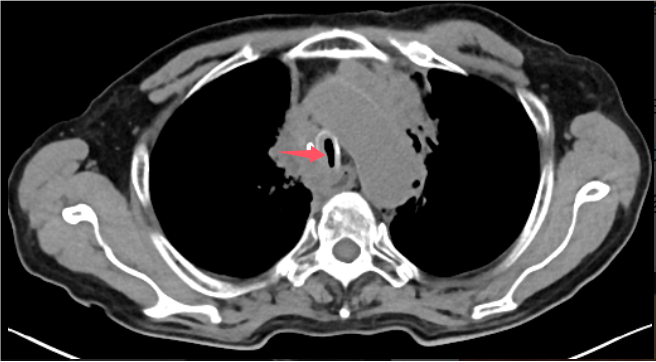

近日,重庆医科大学附属璧山医院(重庆市璧山区人民医院)胃肠(肛肠、疝)外科团队成功实施全院首例完全腹腔镜近端胃切除术+裂隙法食管胃吻合术,为一名82岁的贲门癌患者带来根治希望。该手术突破高龄、肿瘤晚期等多重禁区,标志着我院在腹腔镜胃癌微创治疗领域实现技术跨越,为复杂上消化道肿瘤患者提供了全新解决方案。